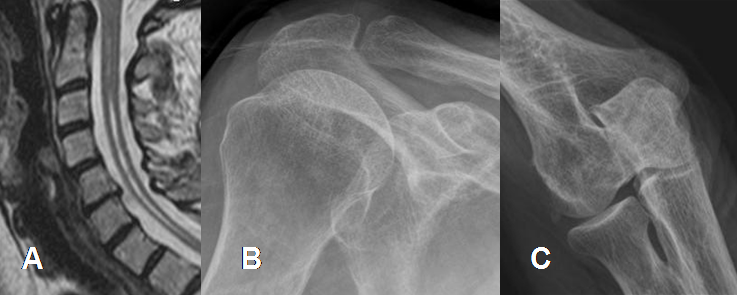

La clave para el Dx temprano depende del factor etiológico. Como principales patologías asociadas se menciona la sífilis o tabes dorsal y el trauma medular, con compromiso de la columna y extremidades inferiores. La siringomelia, con afección de los hombros y la diabetes y otras neuropatías, causan compromiso del pie. (3, 11). (Fig 39 y 40).

Fig 39. Artropatía neuropática.

A: RM sagital en T2. Signos de siringomelia.

B: Rx de hombro AP y C: Rx codo AP. Osteopenia generalizada, por artropatía neuropática.